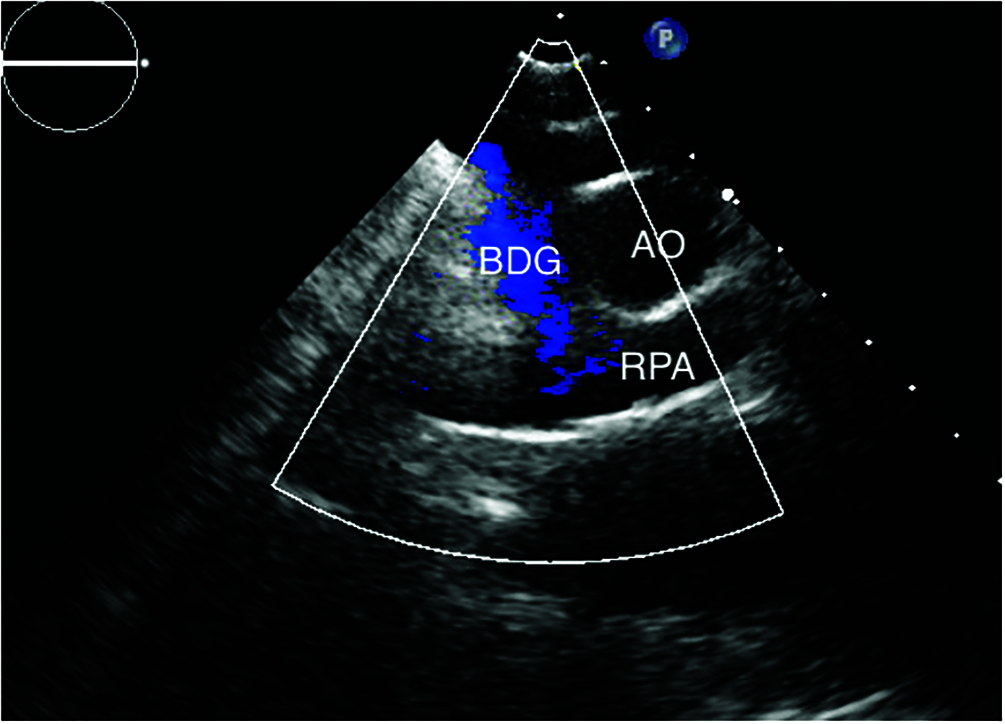

The BDG was evaluated from the suprasternal notch view, a BDG might be right, left sided or bilateral in patients with bilateral superior vena cava. Patent flow was assessed by the presence of laminar flow on color Doppler and with low phasic velocity flow pattern on pulsed-wave Doppler and respiratory variation was also assessed. A significant obstruction was determined by a measured mean gradient of more than 2 mmHg between the BDG circuit and the pulmonary arteries (Fig. 3) [10].

Figure 3: Suprasternal view with color flow showing patent right sided BDG with no reversal of flow in patient number 21 (BDG: bidirectional Glenn, AO: aorta, RPA: right pulmonary artery)